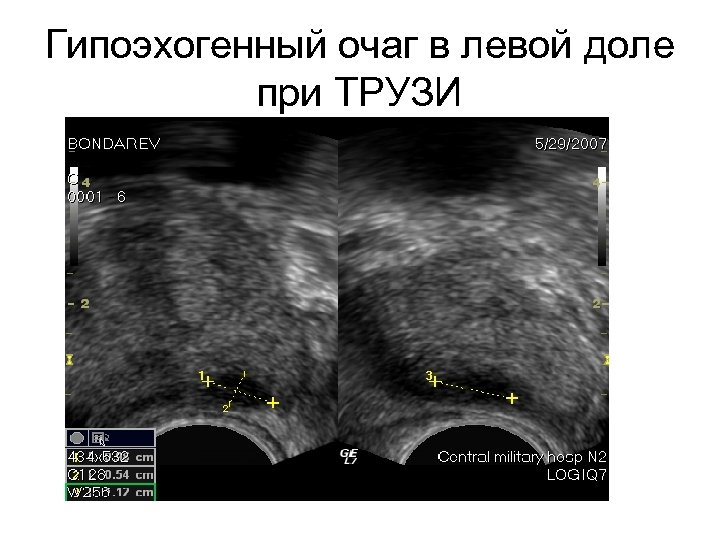

Гипоэхогенный очаг в левой доле при ТРУЗИ